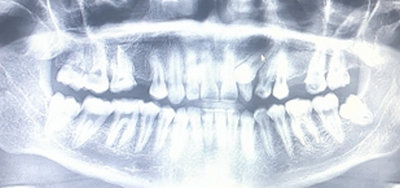

У меня зуб болит. Я его лечила 3 года назад. Мне поставили штифт в декабре 2015, он опять заболел, сделали снимок, оказалось, что он был плохо пролечен. Сняли пломбу, смогли пройти только один канал, во втором канале материал, третий мне врач не смог пройти (инструмент упирался в десну). Тогда еще врач сказал, что этот зуб только удалять, я не согласилась на удаление и мне его просто перекрыли пломбой, теперь опять побаливает.

Как думаете, нужно удалять или его еще можно спасти?

В зубе имеется перфорация, к сожалению, такой зуб спасти и сохранить невозможно.